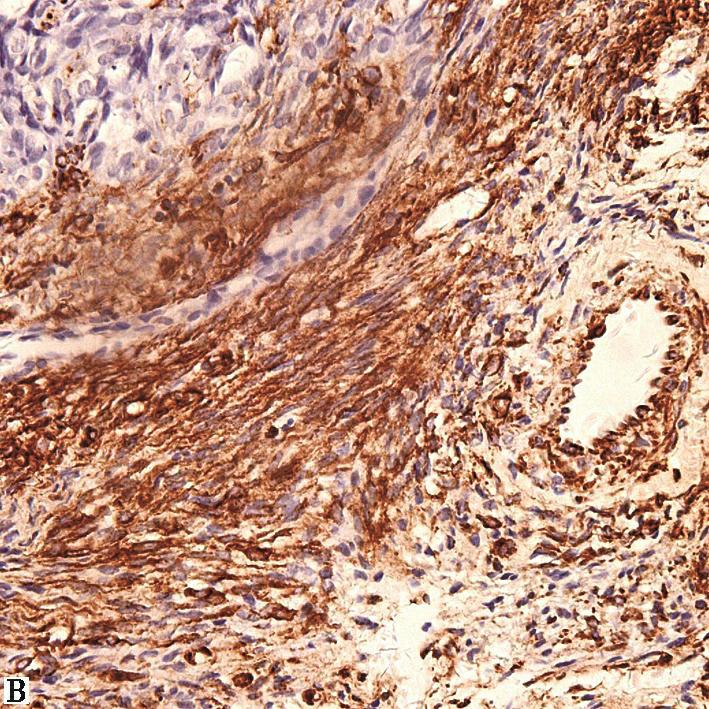

辅助检查:入院后行血常规、生化及结核与风湿免疫相关检验,均未见明显阳性结果,故考虑结核性心包积液可能性较小。后行心电图检查(2015年8月25日)示窦性心律,非特异性ST-T改变。X线胸片(2015年8月25日)示心影向双侧增大,呈烧瓶状。超声心动图(2015年9月1日)示舒张期心包腔内可见液性暗区:左室后壁21mm,右室前壁11mm,左室侧壁30mm,心尖20mm,右房顶10mm,剑突下20mm,心包腔内可见6.6cm×3.5cm实性团块,右室壁轻度受压(图1)。胸部增强CT(2015年8月26日)示心包腔内右心房上方见混杂密度肿块影,最大横截面积约6.1cm×4.0cm,病灶密度不均匀,伴有心包大量积液,少量右侧胸腔积液(图2)。心肌磁共振检查(2015年8月27日)示心包腔内团块状新生物,考虑恶性可能性大(图3)。随后在征得患者及其家属同意后,行PET-CT(2015年8月27日)检查,结果示心包腔内不均匀高代谢肿块,双侧颈根部及锁骨上窝多发高代谢肿大淋巴结,考虑恶性病变可能性大,伴随心包大量积液;右侧胸腔积液;腹、盆腔积液(图4)。综合以上检查及检验结果,考虑患者为恶性心包积液,心包腔内恶性病变可能性大,建议患者行穿刺活检,明确诊断。

图2胸部增强CT